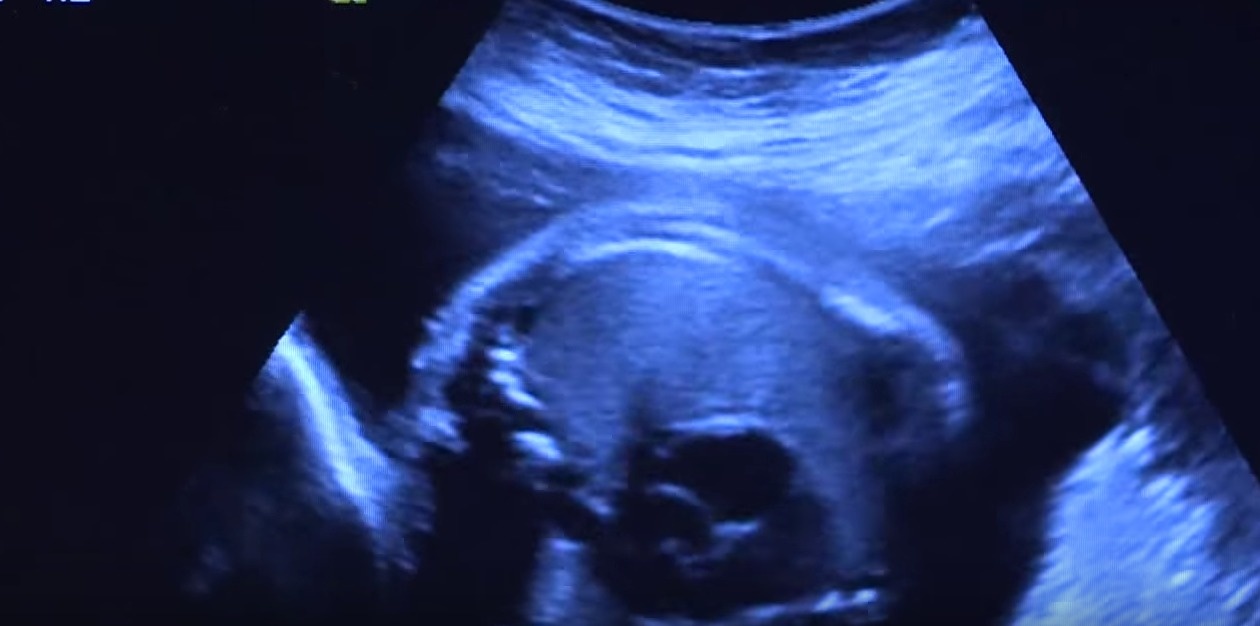

Tuy nhiên, không giống với những phụ nữ khác, sau khi có bầu một thời gian, cơ thể Guillermina bắt đầu có những thay đổi bất thường, bụng to nhanh như trương lên, trên da bụng của cô xuất hiện ngày càng nhiều những vết dạn, vết thâm và bầm tím. Lo lắng về những điều tồi tệ có thể xảy ra, Guillermina đã đến gặp bác sĩ để được tư vấn. Sau khi tiến hành kiểm tra và siêu âm, các bác sĩ đã vô cùng ngạc nhiên khi biết rằng trong bụng của cô có đến 5 thai nhi.

Bác sĩ Tracy Manuck cho biết những vết bầm tím trên bụng của Guillermina là do cô mang những 5 bào thai. Khi chúng cùng lớn dần lên khiến bụng cô to ra nhanh chóng, bụng mẹ quá chật chội nên chúng phải cử động nhiều để tranh giành không gian. Điều này làm cho bụng của Guillermina xuất hiện nhiều vết bầm tím.